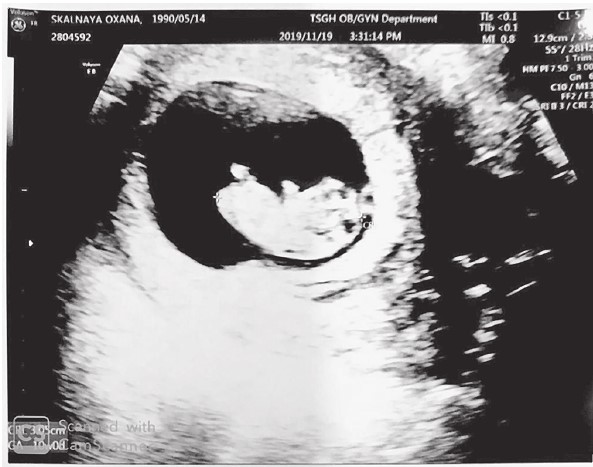

Моей первой внучке Софии,

появления которой на свет мы все ждем с любовью и надеждой,

посвящается!